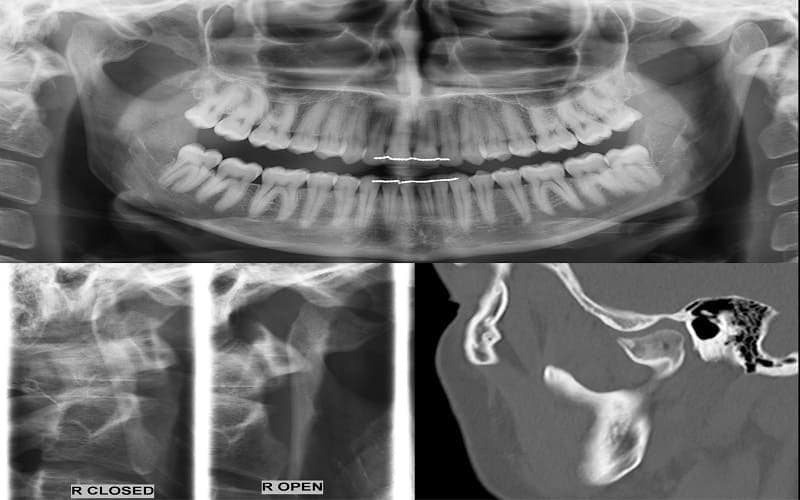

Viêm khớp thái dương hàm là tình trạng khớp nối giữa xương hàm dưới và xương thái dương (nằm ngay trước tai) bị viêm, thoái hóa hoặc rối loạn vận động. Khi khớp này bị tổn thương, người bệnh có thể bị đau vùng hàm và gặp khó khăn khi há miệng, nhai hoặc nói chuyện. Ngoài ra, viêm khớp thái dương hàm cũng có thể gây đau ở các cơ tham gia vận động hàm.

- Rối loạn bên trong khớp: Trong khớp thái dương hàm có một đĩa khớp giúp hàm vận động trơn tru. Khi đĩa khớp bị lệch hoặc vận động không đồng bộ với xương hàm, người bệnh có thể nghe tiếng lục cục, há miệng bị lệch hoặc đôi khi bị kẹt hàm.

- Viêm, thoái hóa khớp hoặc chấn thương: Một số trường hợp viêm khớp thái dương hàm còn liên quan đến chấn thương vùng hàm, viêm khớp hoặc thoái hóa khớp. Những tình trạng này có thể làm tổn thương cấu trúc khớp và gây đau khi cử động hàm.

- Đĩa khớp bị lệch hoặc bị mòn: Đĩa khớp nằm giữa hai đầu xương giúp giảm lực và giúp khớp vận động trơn tru. Khi đĩa này bị lệch hoặc thoái hóa, khớp hàm có thể đau và phát ra tiếng kêu khi cử động.

- Viêm khớp hoặc thoái hóa khớp: Một số bệnh lý khớp như viêm khớp dạng thấp hoặc thoái hóa khớp có thể làm hỏng lớp sụn của khớp thái dương hàm.

- Chấn thương vùng hàm: Va đập mạnh, tai nạn hoặc trật khớp hàm có thể làm tổn thương cấu trúc khớp và gây viêm.